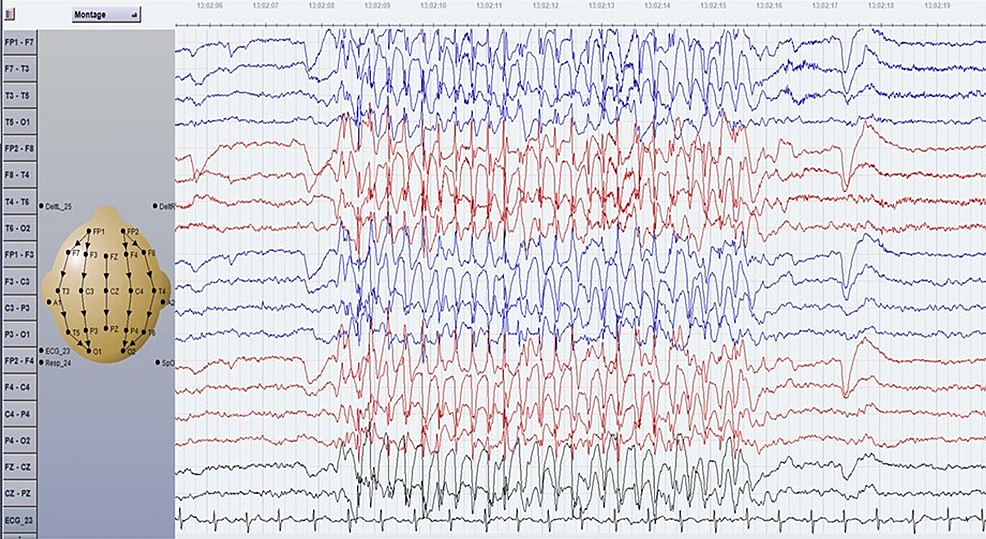

Absence Seizure Eeg

TYPICAL ABSENCE SEIZURE Childhood Absence Epilepsy (CAE) - Petit Mal Epilepsy - Pyknolepsy Childhood Absence Epilepsy | Epilepsy Foundation Frontiers | Absence Seizure Detection Algorithm for Portable EEG Devices | Absence Seizure Eeg